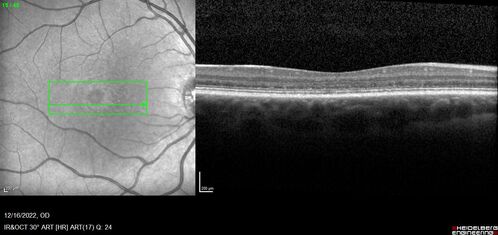

Stargardt Disease - Very Mild - 24 year old

This patient has 3 different ABCA4 mutations. His mother and sister have stargardts and his father has RP. His sisters images are also on Retinagallery.com

stargardt-mild_pacai_121622_35.jpg

Stargardt Sibling - ABCA4 3 mutations

1264 x 596 pixels